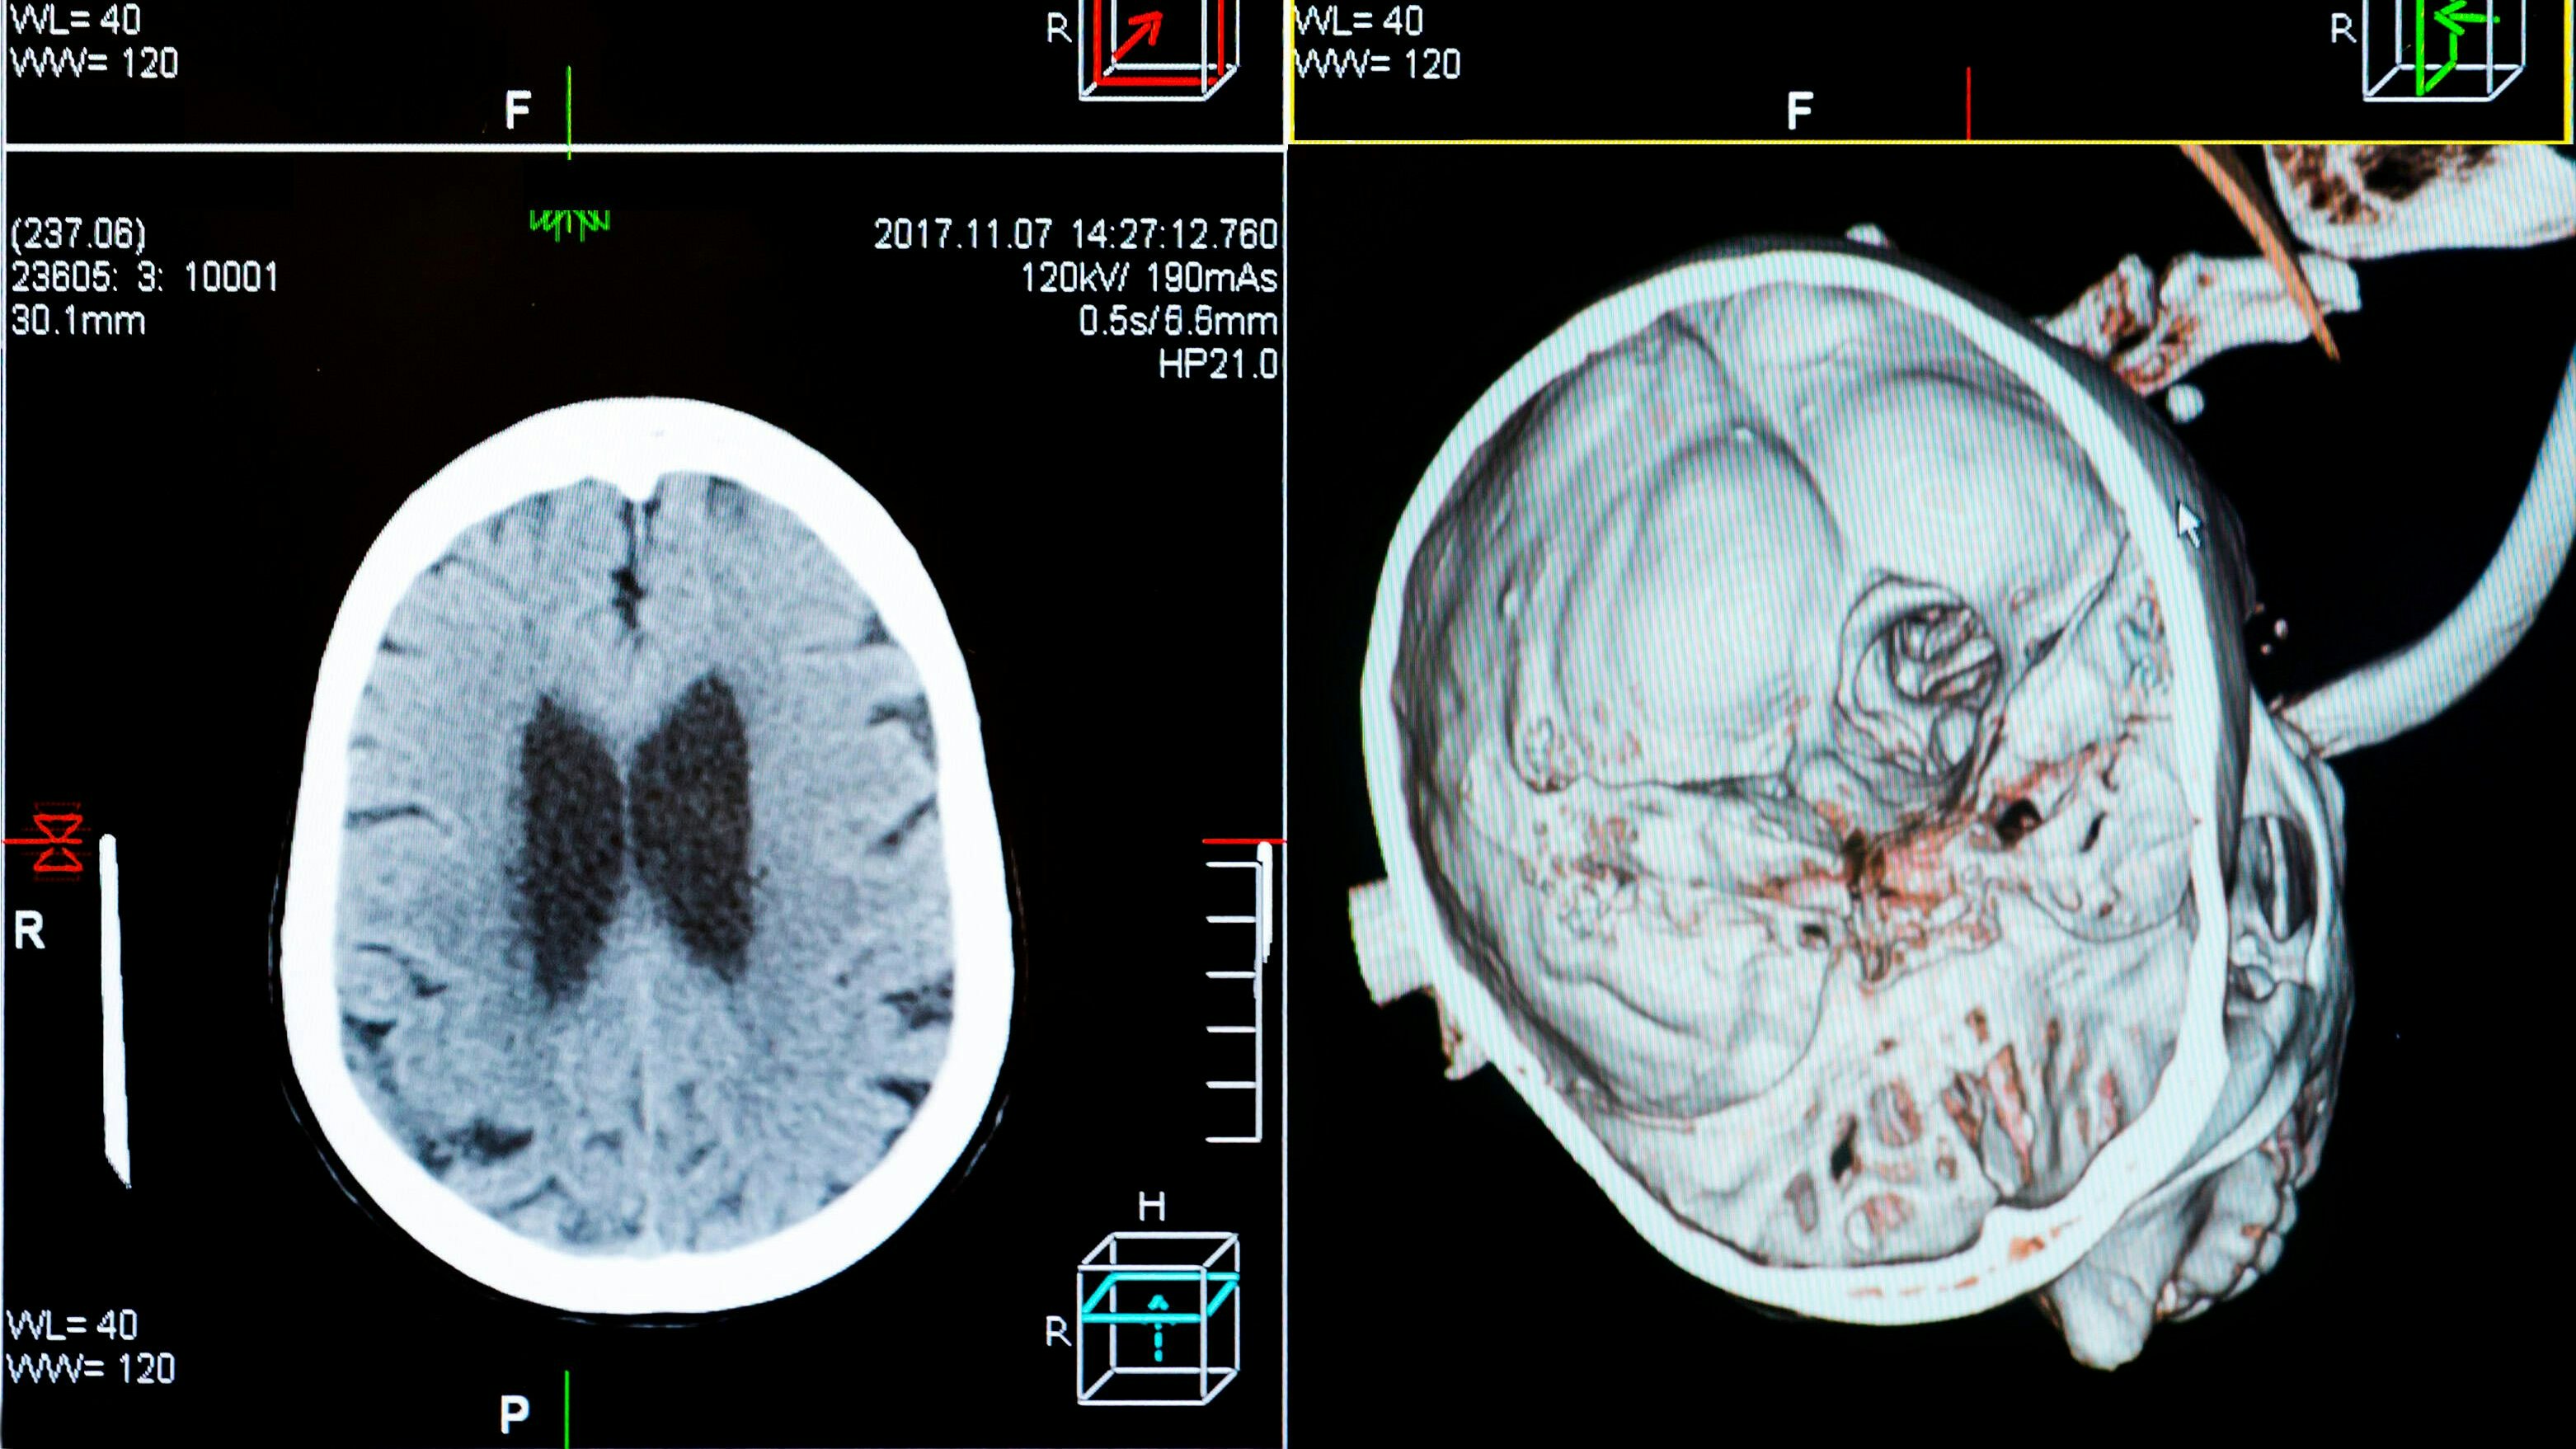

Ein Bub aus Belgien litt an einem "diffusen intrinsischen Ponsgliom" (DIPG), einer sehr aggressiven und bösartigen Form von Hirntumor, die vor allem Kinder betrifft. (Symbolbilder)